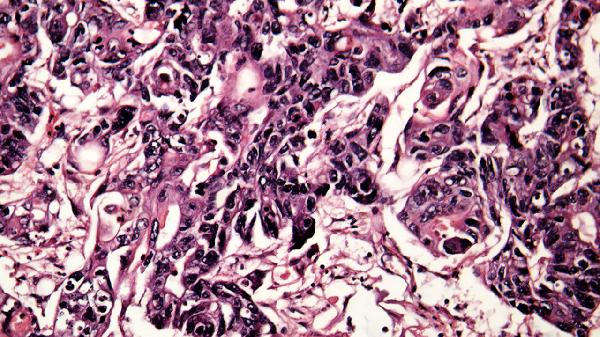

加湿器的储水箱和滤芯长期接触水蒸气,若使用自来水或未及时更换水源,水中的矿物质和微生物可能沉积并繁殖。常见的有害微生物包括军团菌、假单胞菌等,这些细菌通过雾气扩散后可能引发呼吸道感染或过敏反应。建议每1-2天彻底清洗水箱并用白醋或专用清洁剂消毒,每周更换一次滤芯,使用蒸馏水或纯净水可减少矿物质沉淀。

部分加湿器设计存在死角清洁困难,超声波式加湿器因直接雾化水质问题更为突出。若发现水箱壁有滑腻感或异味,说明已存在生物膜,需立即停机清洁。免疫力较低的人群如婴幼儿、老年人更需注意,可选择带有紫外线杀菌功能或冷蒸发式加湿器。